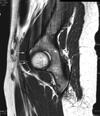

An 18-year-old man sustains a twisting injury to the left knee while playing football. An MRI scan is shown in Figure 48. What is the most likely diagnosis?

lateral mensicus tear

MRI scan shows a displaced, bucket-handle lateral meniscus tear. The sagittal view shows the typical “large anterior horn” sign, or “double meniscus” sign in which the displaced bucket-handle fragment appears just anterior to the native anterior horn of the lateral meniscus. The presence of the fibula on the sagittal view confirms this as the lateral compartment. The image is lateral and the cruciate ligaments are not visualized. The articular cartilage shown does not demonstrate an osteochondral lesion.